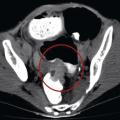

Tomodensitométrie abdomino-pelvienne (fig. 4, 5) :

• 1) Elle fait le diagnostic positif de l’occlusion (présence d’anses grêles dilatées de diamètre supérieur ou égal à 25 mm si la valvule de Bauhin est incontinente et d’une partie du côlon de diamètre supérieur ou égal à 60 mm en amont de la tumeur).

• 2) Elle détermine la topographie (colique).

• 3) Elle détermine l’étiologie : l’adénocarcinome se traduit par un épaississement dédifférencié et sténosant de la paroi digestive en virole avec parfois infiltration de la graisse adjacente et adénomégalies péritumorales.

• 4) Elle identifie des signes de gravité (perforation, pneumatose pariétale, anomalies de rehaussement des anses spécialement sur le cæcum) (fig. 5).

• 5) Elle fait un bilan d’extension (fig. 5).